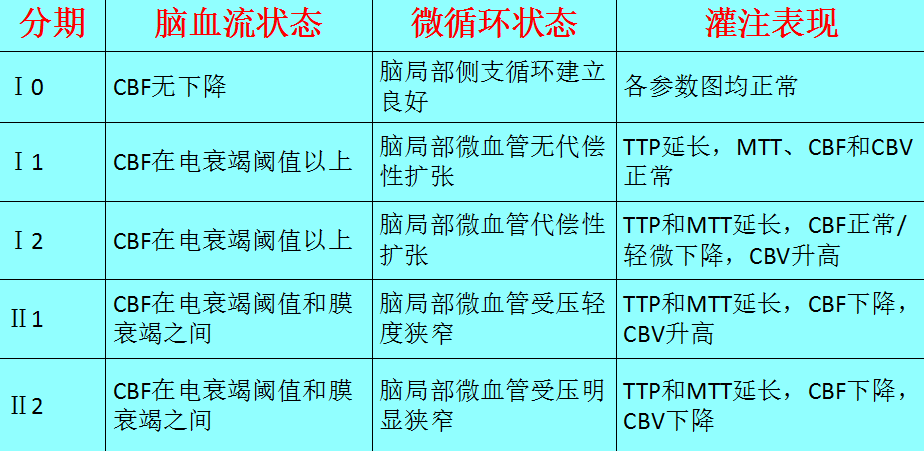

表1 脑局部缺血的病理生理变化

表2 脑梗死前期脑局部缺血影像分期